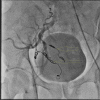

The Endovascular Embolization of an Isolated Internal Iliac Artery Aneurysm: A Case Report

While isolated internal iliac artery aneurysms (IIIAAs) are rare entities, they are associated with a high mortality rate if ruptured. IIAAs are usually asymptomatic and can be discovered accidentally during imaging for any other causes. The treatment options vary according to the signs, symptoms, size of the aneurysm, and the patient's general condition. While surgery used to be the first option of treatment earlier, with the advances in the field of endovascular intervention, endovascular repair of IIIAA has emerged as the first option of treatment if applicable.